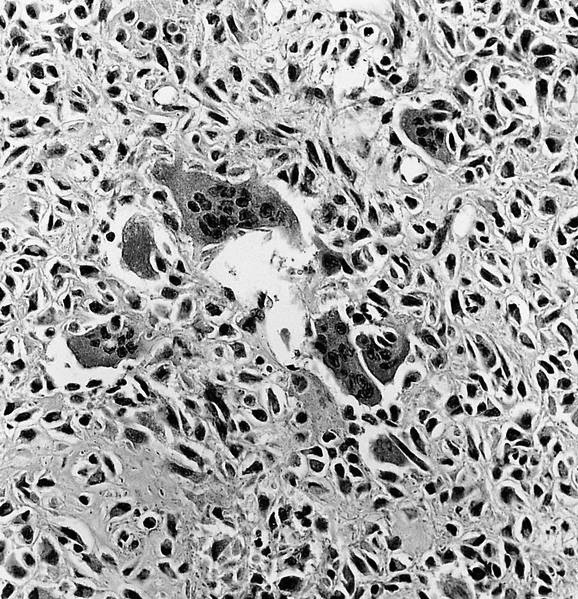

Microscopic (histologic) description

- Composed of round or polyhedral chondroblasts with abundant eosinophilic cytoplasm and well defined cell borders; spindle shaped cells may be focal (Ann Diagn Pathol 2003;7:205, Cancer 1972;30:401)

- Nuclei are oval, hyperlobulated with grooves

- Pericellular lace-like or chicken wire type calcification among degenerative chondroblasts

- Chondroid matrix almost always present (pink rather than blue matrix)

- May have marked cellularity, intracytoplasmic glycogen granules, mitotic figures, necrosis and osteoclast type giant cells

- No significant nuclear atypia as compared with malignant chondroblastoma (Mod Pathol 2020;33:2295)

- Aneurysmal bone cyst-like change is common (Skeletal Radiol 2010;39:583)

Microscopic (histologic) images

An 18 year old man presents with a 3 cm, well defined lucent lesion within the epiphysis of the distal femur. Microscopic features of the surgical curettage specimen are represented by the H&E images. The best diagnosis is

A. Chondroblastoma. Chondroblastomas commonly present in the second decade of life as a singular, well defined lucent lesion within skeletally immature long bones. Characteristic histopathological features include sheets of chondroblasts admixed with osteoclast-like giant cells in a chondroid matrix and focal chicken wire type calcification. Chondroid fibromas typically lack chicken wire type calcification. Chondroblastoma-like osteosarcomas generally display an infiltrative growth pattern with marked cytologic atypia. Chondroid matrix is not commonly seen in giant cell tumor of bone.